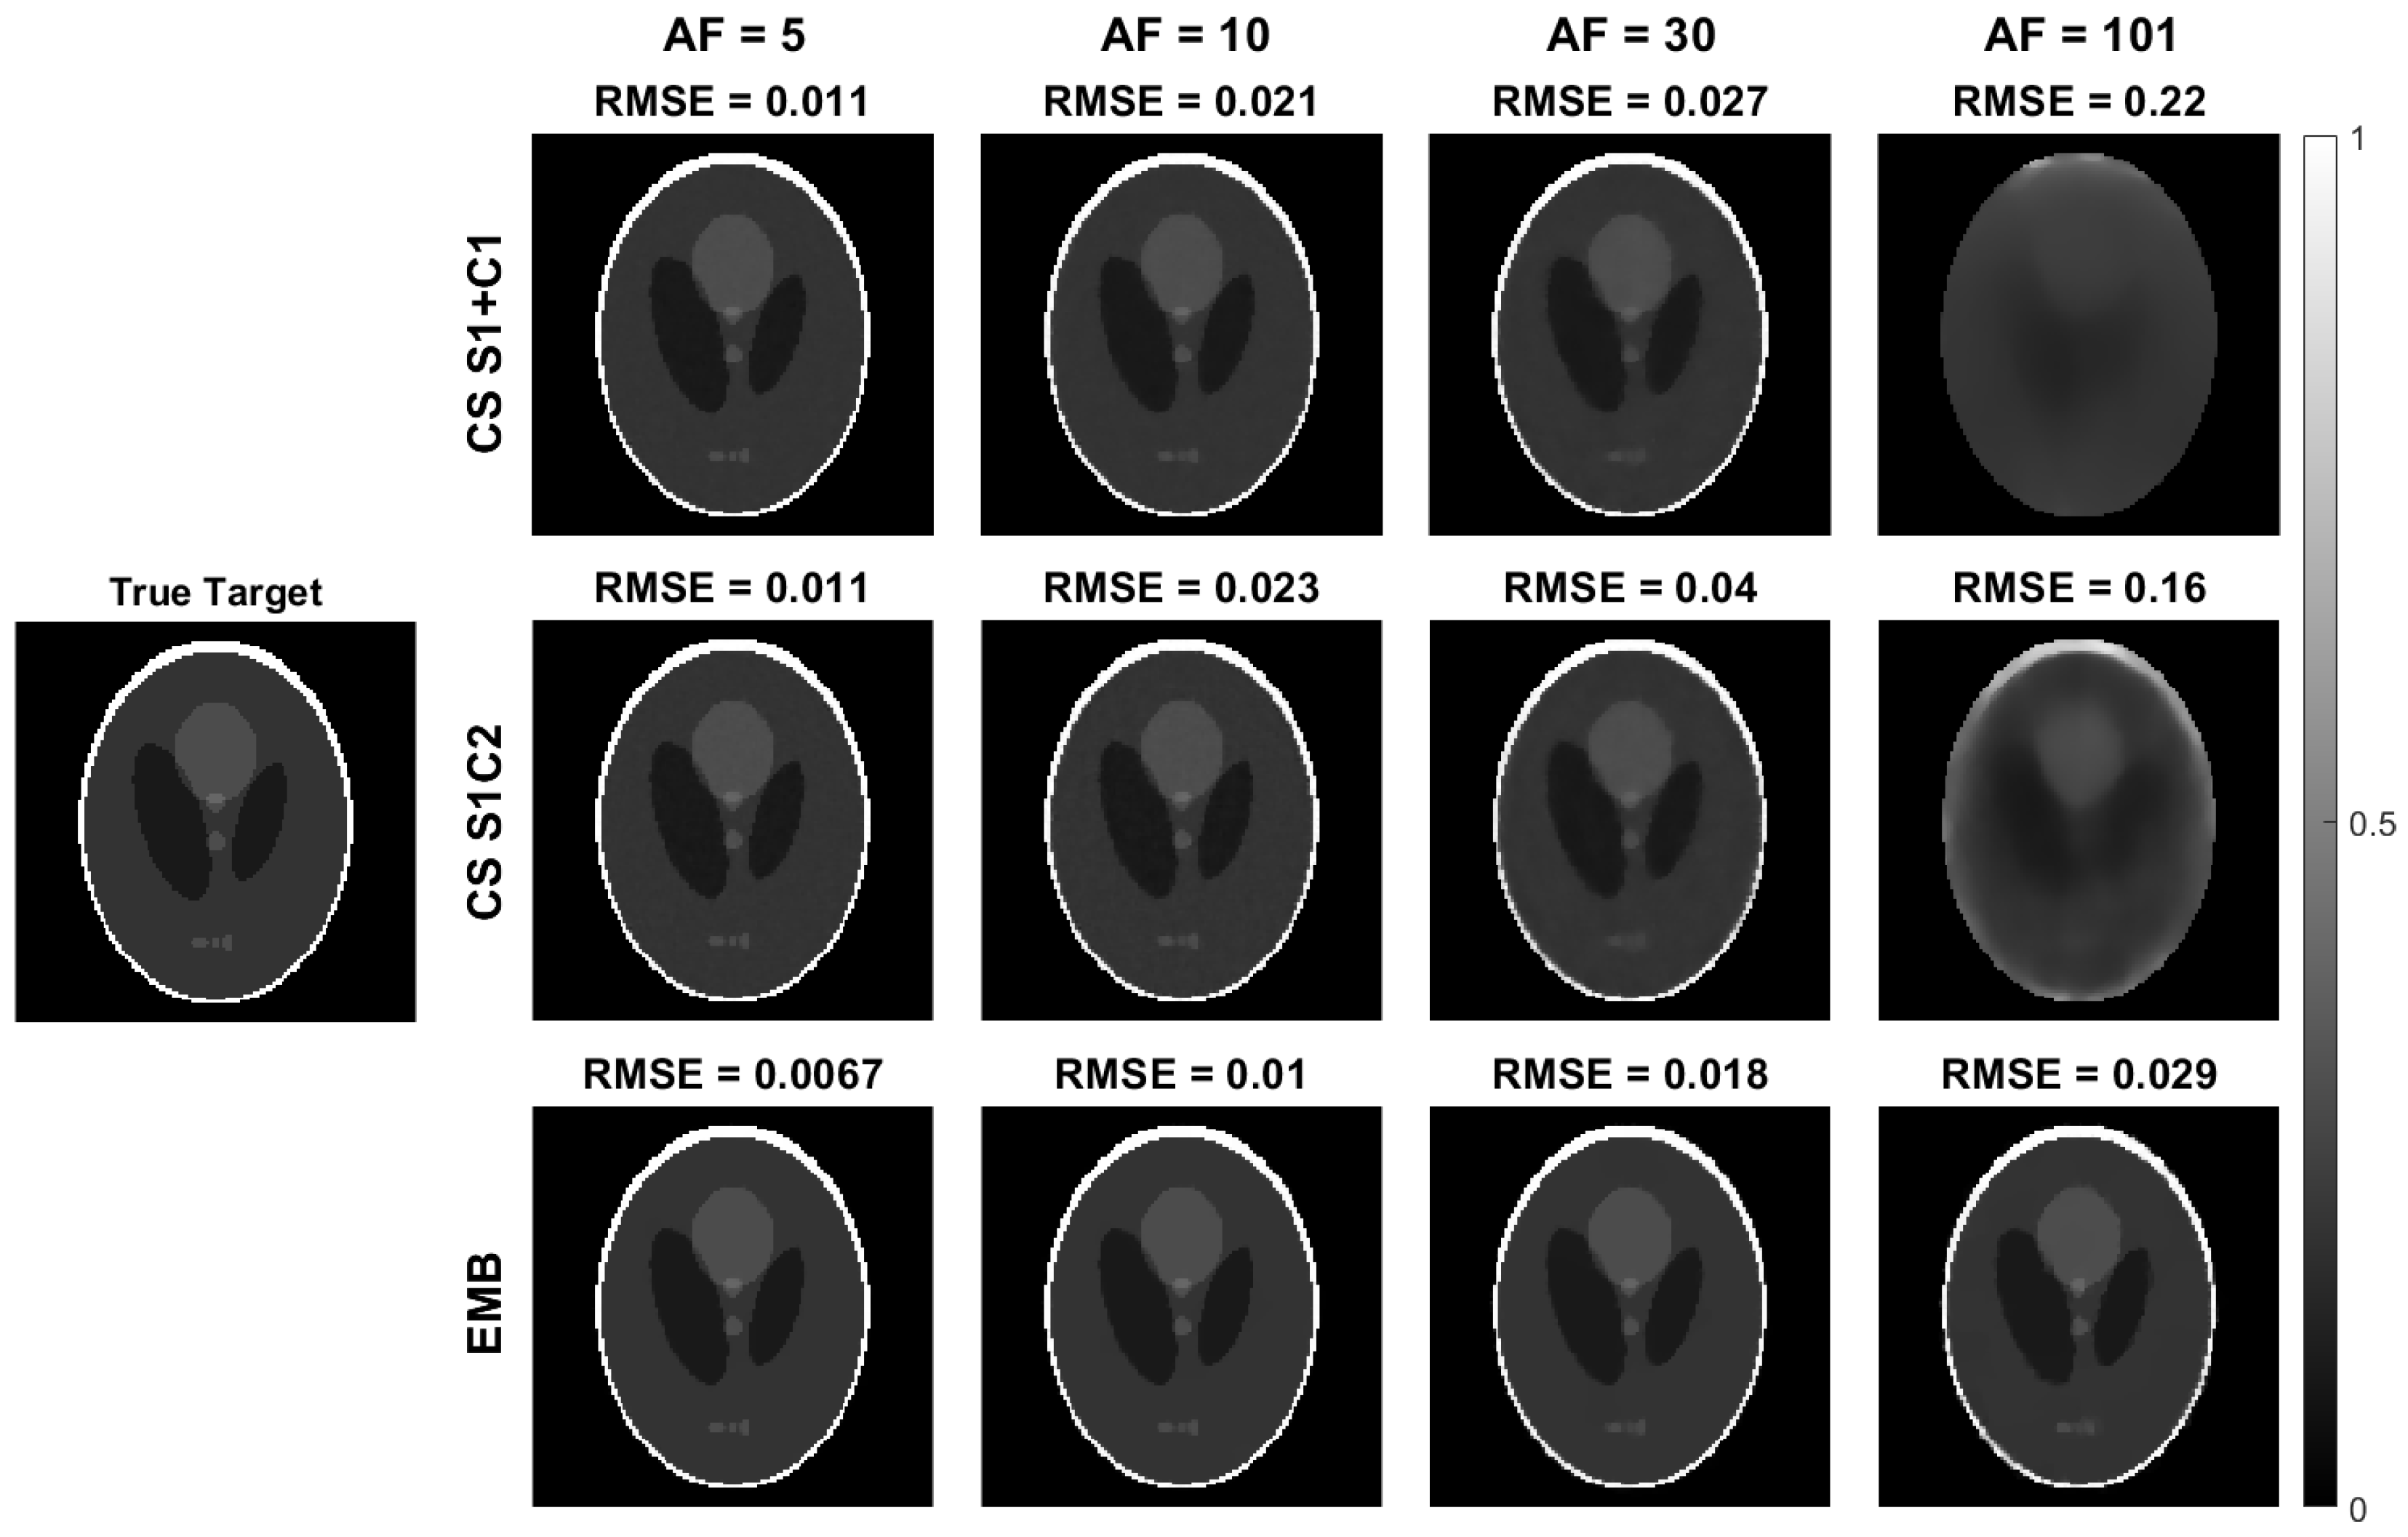

4.1. Simulated Golden Angle Radial Data